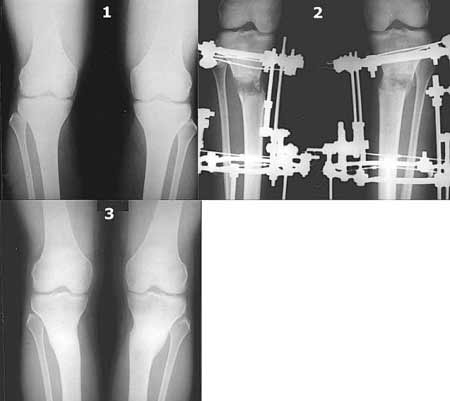

a> Совершщенно беспредметный спор. Лучше бы спорили как менее травматично

Как уже писал, вчера сделал одну ногу (может, свой плюс будет что не обе- вдвое меньше травма, сразу на костыли встанет, оперированную ножку немного разомнет, тут и вторую заделаем).

Операция была интересной, много полезного опыта приобрел.

Снимки в приложении - фас сравнительный с неоперированной ногой. Жду критики.

Впрос про остеотомию большеберцовой непраздный. Эта получилась при надломе несколько более наклонно, чем я делал (сейчас проблема,

как на второй ноге сделать так же). Вот этот высоящий "зуб" центрального отломка не заменит ли в плане косметики то, что получается при медиализации дистального?

|